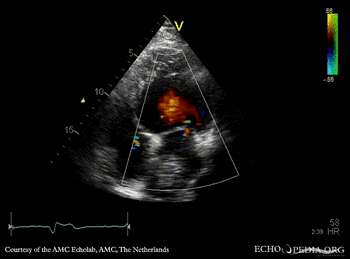

| A3CH | A4CH with Color Doppler: moderate mitral regurgitation |